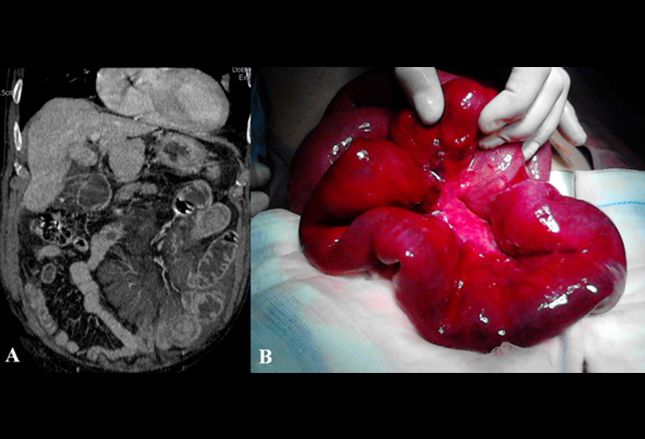

图象显示急性肠系膜缺血患者肠系膜静脉血栓形成术前二维多层螺旋CT,冠状面(A),术中的图像(B)。